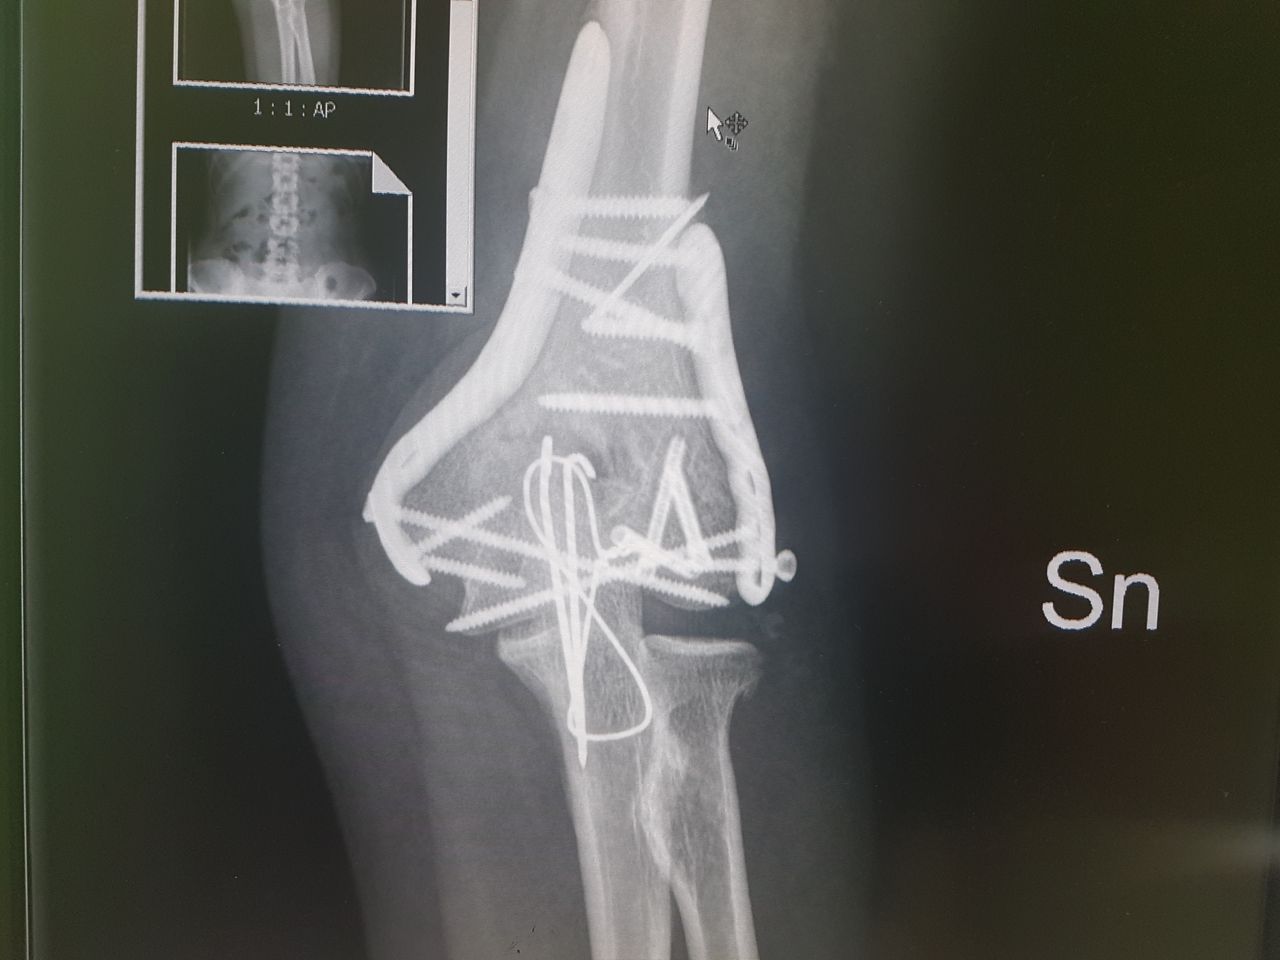

Specialista di chirurgia della Spalla, del Gomito e di traumatologia dello sport. Opinion leader e docente di fama Europea della patologia dell'arto superiore, con particolare interesse verso le ricostruzioni legamentose, l'artroscopia, la sostituzione protesica ed interventi di revisione. Gran parte della mia pratica clinica e chirurgica è attualmente il trattamento di fallimenti di altri interventi o traumi non guariti correttamente e il trattamento dell'atleta ad alto livello con patologie di spalla e gomito.

Parallelamente all'attività chirurgica di revisione ho da sempre approfondito la chirurgia mini invasiva dell'arto superiore, soprattutto sviluppando techniche chirurgiche come l'artroscopia di gomito e la fissazione esterna per le fratture di omero prossimale.

Most of my surgical practice is currently the treatment of failures of prior surgeries and post traumatic deformities. I'm also greatly involved in the treatment of high level athletes and I developed my skills in mini-invasive surgeries, especially elbow arthroscopy and mini-invasive techniques for the treatment of proximal humeral fractures.